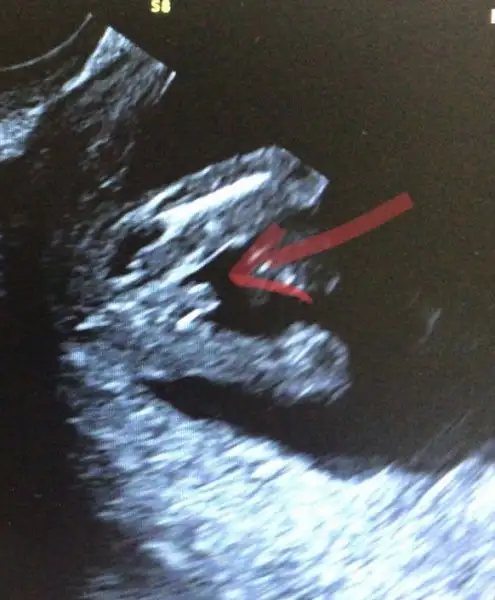

Eğer düzgün bakabiliyosam ve üst üste duranlar bacakları ise, ortada duran bişey var ve bence erkekKızlar meraba bugün doktordan geldik

Bir tek erkekler bu kadar cins bir duruş yapar herhaldeBaştan atayım o zaman

Eğer düzgün bakabiliyosam ve üst üste duranlar bacakları ise, ortada duran bişey var ve bence erkek![]()

Bir tek erkekler bu kadar cins bir duruş yapar herhalde

Aaaaa bildiğin pipi bu

Gönlünden geçen ne peki canım, bence erkek o çıkıntııEvet bacakları